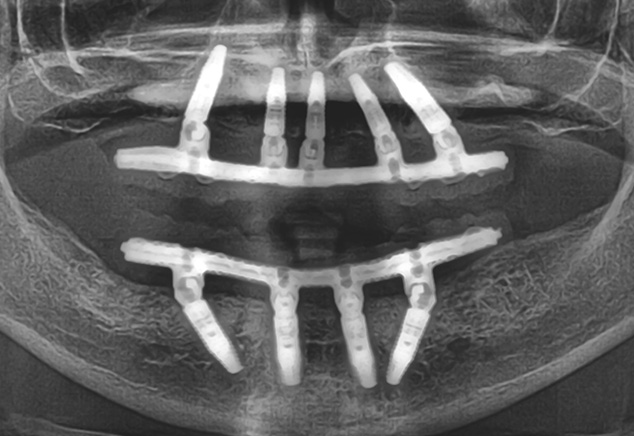

The implant sites were prepared using the manufacturer's protocol (except for bone tapping) for the Straumann BLT implant. The implants were placed using the surgical guide template with the following insertion torques measured: site: #4, #7, #8-9,#11,#13, #21,#23,#26. All torques were >35Ncm with #28 recording 20Ncm insertion torque values. All implants were 4.1mm in diameter and 14mm in length except #7, #8-9, and #11, which were 12mm in length (Fig 7). All 17 and 30 degree-angled implants were bone profiled prior to SRA abutment placement. This allowed the complete seating of the SRA abutment at the recommended 35Ncm torque. Using the available Straumann bone profilers with the appropriate Narrow Connection (NC) or Regular Connection (RC) inserts was a critical step for an abutment to fit correctly. The following SRA abutments (all were 2.5mm gingival heights) were then chosen: straight: #23, #26; 17 degrees: #4, #7, #8-9; and 30 degrees: #11, #13, #21, and #28. Tall protective healing caps were then placed (Fig 8), and the dentures were checked to evaluate that there was adequate space for the pink acrylic to allow for bite registration material thickness. All sockets and buccal gaps to the immediately placed implants were bone grafted. Prior to suturing, the tissue flaps were scalloped with 15c blades to reduce overlap of the flaps over the protective caps. This not only aided in post-operative healing, but also aided in the visualization of the abutments by the restorative dentist for the provisional insertion. The patient was sutured with resorbable 4-0 chromic gut and 5-0 Vicryl™ sutures (Ethicon: Johnson & Johnson) and was released to be seen immediately by Dr. Randel for the coordinated restorative visit. As discussed below, his responsibilities included: bite registration, impressions, and the dental lab conversion of the complete denture to a metal reinforced fixed transitional prosthesis (indirect provisionalization technique). Our team of restorative dentists have been treating full-arch immediately loaded cases on 5-8 implants (depending if restoration is a hybrid or C&B) since 1994. Our earlier experiences, for approximately the first two years (1994-1996), have us all presently using the indirect technique, which in our hands is easier for everyone involved (especially the patient). We handle these coordinated visits between offices, the dental lab, and our Straumann representative weeks prior so we are all on the same page with timing. These coordinated efforts could be compared to a symphony orchestra, where each musician knows their specific part and when and where they are expected to be. Many of our patients have described this fluidity as a seamless experience that they witness first hand and greatly appreciate.

The next afternoon, the prostheses were inserted (Fig 10) and panoramic radiographic confirmation of proper seating was obtained (Fig 11). Any necessary occlusal adjustments were then completed. The patient was then seen every 2-3 weeks for deplaquing and plaque control review per our earlier discussed protocol. The occlusion was also refined as needed. A water irrigation device was given and reviewed at 6 weeks post-surgery.